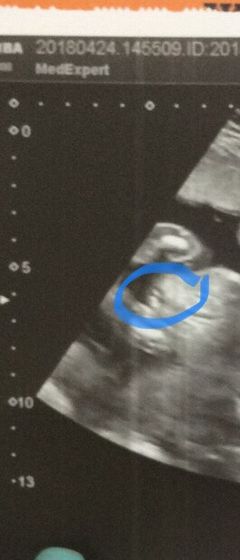

На втором УЗИ подтвердили 100%что девчонка. У нас будет доча. Но мы с папой по ходу так мечтали о сыне днём и ночью бредили.Что получив фото нам кажется что там мальчик ????

Видно же что "пирожок" ? поздравляю?

Спасибо.Марин а у нас по ходу глюки????.Просто очень хотели сына а потом дочь и долго не получалось но вот получилась дочь.